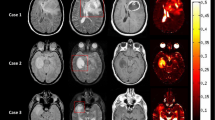

R2* response maps

All T2*-weighted images were of good quality with respect to motion and susceptibility artefacts. Figure 1 displays the results of R2* response mapping as obtained from the voxel-wise t-test of the dynamic R2* series. In ‘non-tumoral’ tissue, the strongest R2* decrease occurred in and around cerebral sulci, where voxels contain veins and/or grey matter with a high blood volume. R2* changes within the superior sagittal sinus were found to be between −19 s-1 and −31 s-1 for carbogen and between −13 s-1 and −27 s-1 for CO2/air. The lowest R2* changes were found in white matter, where negative and positive changes of up to ±0.5 s-1 were detected. Small positive changes were also detected in the ventricles and partly in the sulci. Response patterns differed between tumour entities and specific areas within each tumour.

R2* response of human tumours. From left to right the T2-weighted images T2 TSE, the contrast agent-enhanced T1-weighted images T1 CE (with the exception of patient P5, where the subtraction of the T1 CE and T1 images is given), the ADC maps, the R2* maps of the first dynamic (during air breathing), and the overlay maps of significant R2* changes (ΔR2*) during carbogen and CO2/air inhalation are displayed for all examined patients (see Table 1). ‘T’, ‘N’, ‘E’ and ‘X’ denote the defined ROIs in the ‘contrast-enhancing’ tumour area, ‘necrosis’, ‘oedema’, and ‘non-tumoral’ tissue, respectively. Voxels with significant R2* decrease (ΔR2* < 0) and increase (ΔR2* > 0) are displayed colour-coding (white to red and light blue to dark blue, respectively). The colours scale linearly with the mean difference between the baseline and response data used in the t-test (p = 0.05). The underlying images are peak height images (sum of all echoes) of the first dynamic. Two different responses are seen in meningioma. A well-perfused meningioma (WHO I°, P1) shows a decrease in R2* for both gases whereas a hypoperfused meningioma (WHO II°, P2) displays no change or minimal increase in R2* likely related to a low density of functional vessels and a lack of normal vasoreactivity. A decrease in R2* for both gases indicating good vascularisation and ‘normal’ vasoreactivity is seen in the ring-shaped well perfused enhancing tumour area in a glioblastoma (P4) and a metastasis (P5). Mixed responses to CO2/air are found in the ‘contrast-enhancing’ tumour area of another glioblastoma (P3). The necrotic centre of the lesions and the perifocal ‘oedema’ reveal typically voxels with increased or unchanged R2* values for both gases

Table 4 summarises the fractions of negatively, positively and non-responding voxels for the investigated ROIs. ‘Non-tumoral’ tissue showed predominantly negative R2* changes for carbogen in all cases and in 5/7 cases also for CO2/air. The amount of voxels with increased R2* was less than 32% in all cases. In the ‘contrast-enhancing’ tumour area negative R2* changes were observed in 5/7 and 4/7 patients for carbogen and CO2/air, respectively. One hypoperfused meningioma (P2) and one lymphoma (P7) hardly responded to either of the two challenges. A larger metastasis (P6) was only sensitive to carbogen. Areas of ‘necrosis’ and perifocal ‘oedema’ (with the exception of P1) showed voxels with increased or unchanged R2* values for both respiratory challenges regardless of tumour histology. Generally, the response in tumour tissue was more heterogeneous than in ‘non-tumoral’ tissue and the spatial distribution of R2* changes within the tumour varied between subjects.